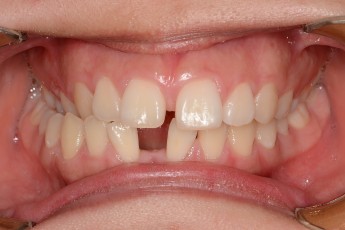

Before

After